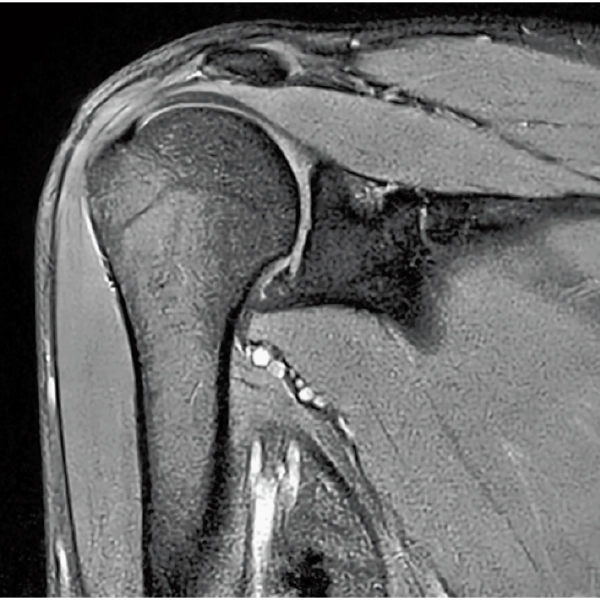

High Resolution

T2WI, 0.56×0.70×3.0mm, 2:28

T2*WI Multi Echo,

0.38×0.38×2.0mm

0.35×0.40×3.0mm, 2:55